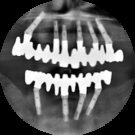

Guided Surgery